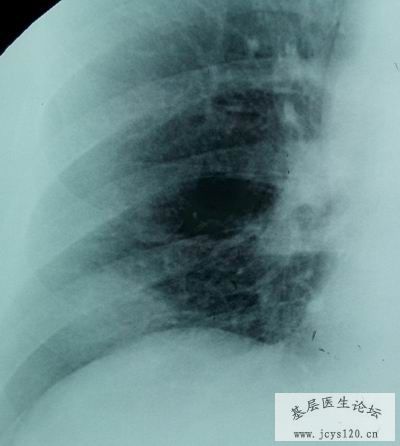

患者,男,64岁,咳嗽,低热半月余,血象,白细胞9.7白细胞X109,血沉37mm/h,影像表现如图: 请大家分析一下是肺结核还是肺癌呢 阅读全文>

诊断报告: 两侧胸廓对称,气管上纵隔居中,双肺门影不大。正位可见右肺中下野内侧带可见一片状高密度影,边界模糊;侧位于胸骨、膈面成角处,密度较高,边界清晰,与右肺的叶间裂重合。余肺纹理增粗 ... 阅读全文>